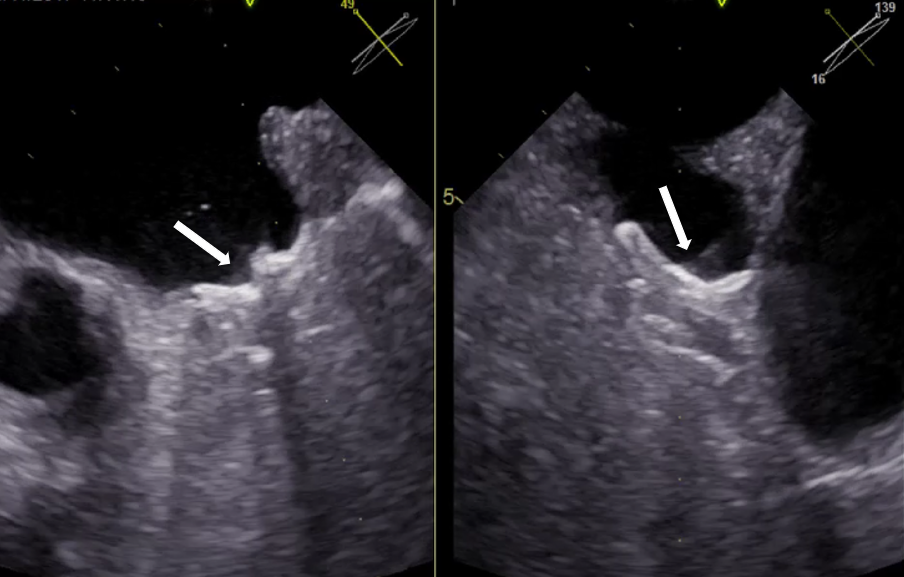

Skopia rentgenowska – okluder w uszku lewego przedsionka przed odłączeniem od systemu dostawczego

Kwalifikacja do zabiegów prowadzona jest na Oddziale Chorób Strukturalnych Serca, którego koordynatorem jest prof. Marcin Fijałkowski z I Katedry i Kliniki Kardiologii GUMed. Kluczową rolę w planowaniu zabiegów odgrywa echokardiografia przezprzełykowa i tomografia komputerowa serca. Szczegółową analizą obrazów tomografii komputerowej zajmuje się prof. Edyta Szurowska kierująca II Zakładem Radiologii GUMed oraz dr Dorota Kulawiak-Gałąska z Zakładu Radiologii naszego Uniwersytetu.